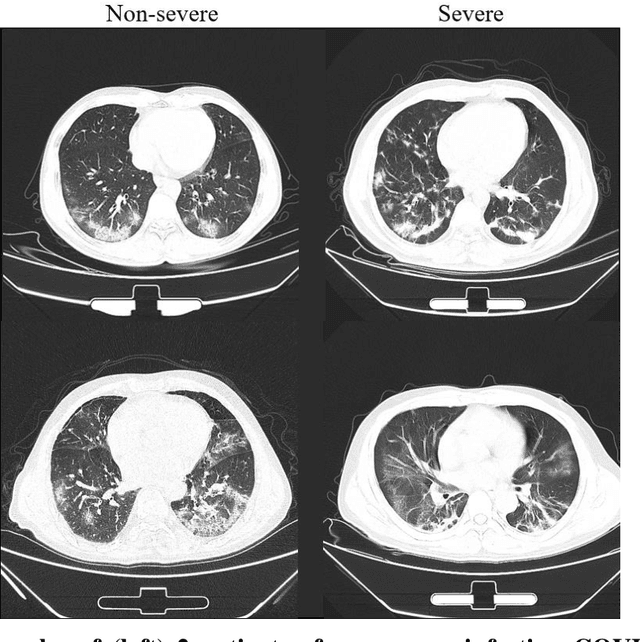

Abstract:Background: Chest computed tomography (CT) is recognized as an important tool for COVID-19 severity assessment. As the number of affected patients increase rapidly, manual severity assessment becomes a labor-intensive task, and may lead to delayed treatment. Purpose: Using machine learning method to realize automatic severity assessment (non-severe or severe) of COVID-19 based on chest CT images, and to explore the severity-related features from the resulting assessment model. Materials and Method: Chest CT images of 176 patients (age 45.3$\pm$16.5 years, 96 male and 80 female) with confirmed COVID-19 are used, from which 63 quantitative features, e.g., the infection volume/ratio of the whole lung and the volume of ground-glass opacity (GGO) regions, are calculated. A random forest (RF) model is trained to assess the severity (non-severe or severe) based on quantitative features. Importance of each quantitative feature, which reflects the correlation to the severity of COVID-19, is calculated from the RF model. Results: Using three-fold cross validation, the RF model shows promising results, i.e., 0.933 of true positive rate, 0.745 of true negative rate, 0.875 of accuracy, and 0.91 of area under receiver operating characteristic curve (AUC). The resulting importance of quantitative features shows that the volume and its ratio (with respect to the whole lung volume) of ground glass opacity (GGO) regions are highly related to the severity of COVID-19, and the quantitative features calculated from the right lung are more related to the severity assessment than those of the left lung. Conclusion: The RF based model can achieve automatic severity assessment (non-severe or severe) of COVID-19 infection, and the performance is promising. Several quantitative features, which have the potential to reflect the severity of COVID-19, were revealed.